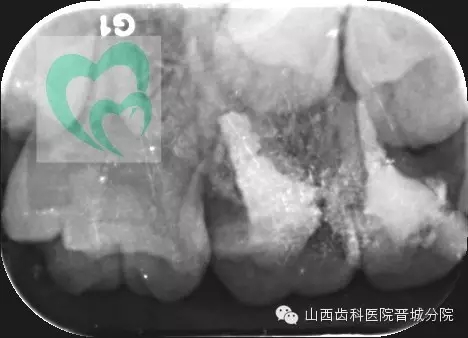

兒童乳牙金屬預(yù)成冠(preformed metalcrown,PMC)是一個(gè)預(yù)先成型的、與牙齒非常貼合的不銹鋼金屬牙冠,套在乳牙上可以保護(hù)牙齒并加強(qiáng)牙齒的強(qiáng)度、恢復(fù)患牙正常咬合關(guān)系等,有效保護(hù)缺損較大的乳磨牙至替牙期,從而保證繼承恒牙順利萌出。   對于乳磨牙齲損,臨床傳統(tǒng)采用玻璃離子及光固化樹脂充填,但由于乳牙體積小、牙冠短、牙體硬組織薄、洞型制備深度有限等問題,其固位形及抗力形較差,充填物易脫落,最終導(dǎo)致治療失敗。而乳牙預(yù)成冠的使用能很好的解決上述問題。

下面展示一例由我院龐超醫(yī)生操作并整理資料的兒童乳牙預(yù)成冠病例。

來源于山西齒科醫(yī)院